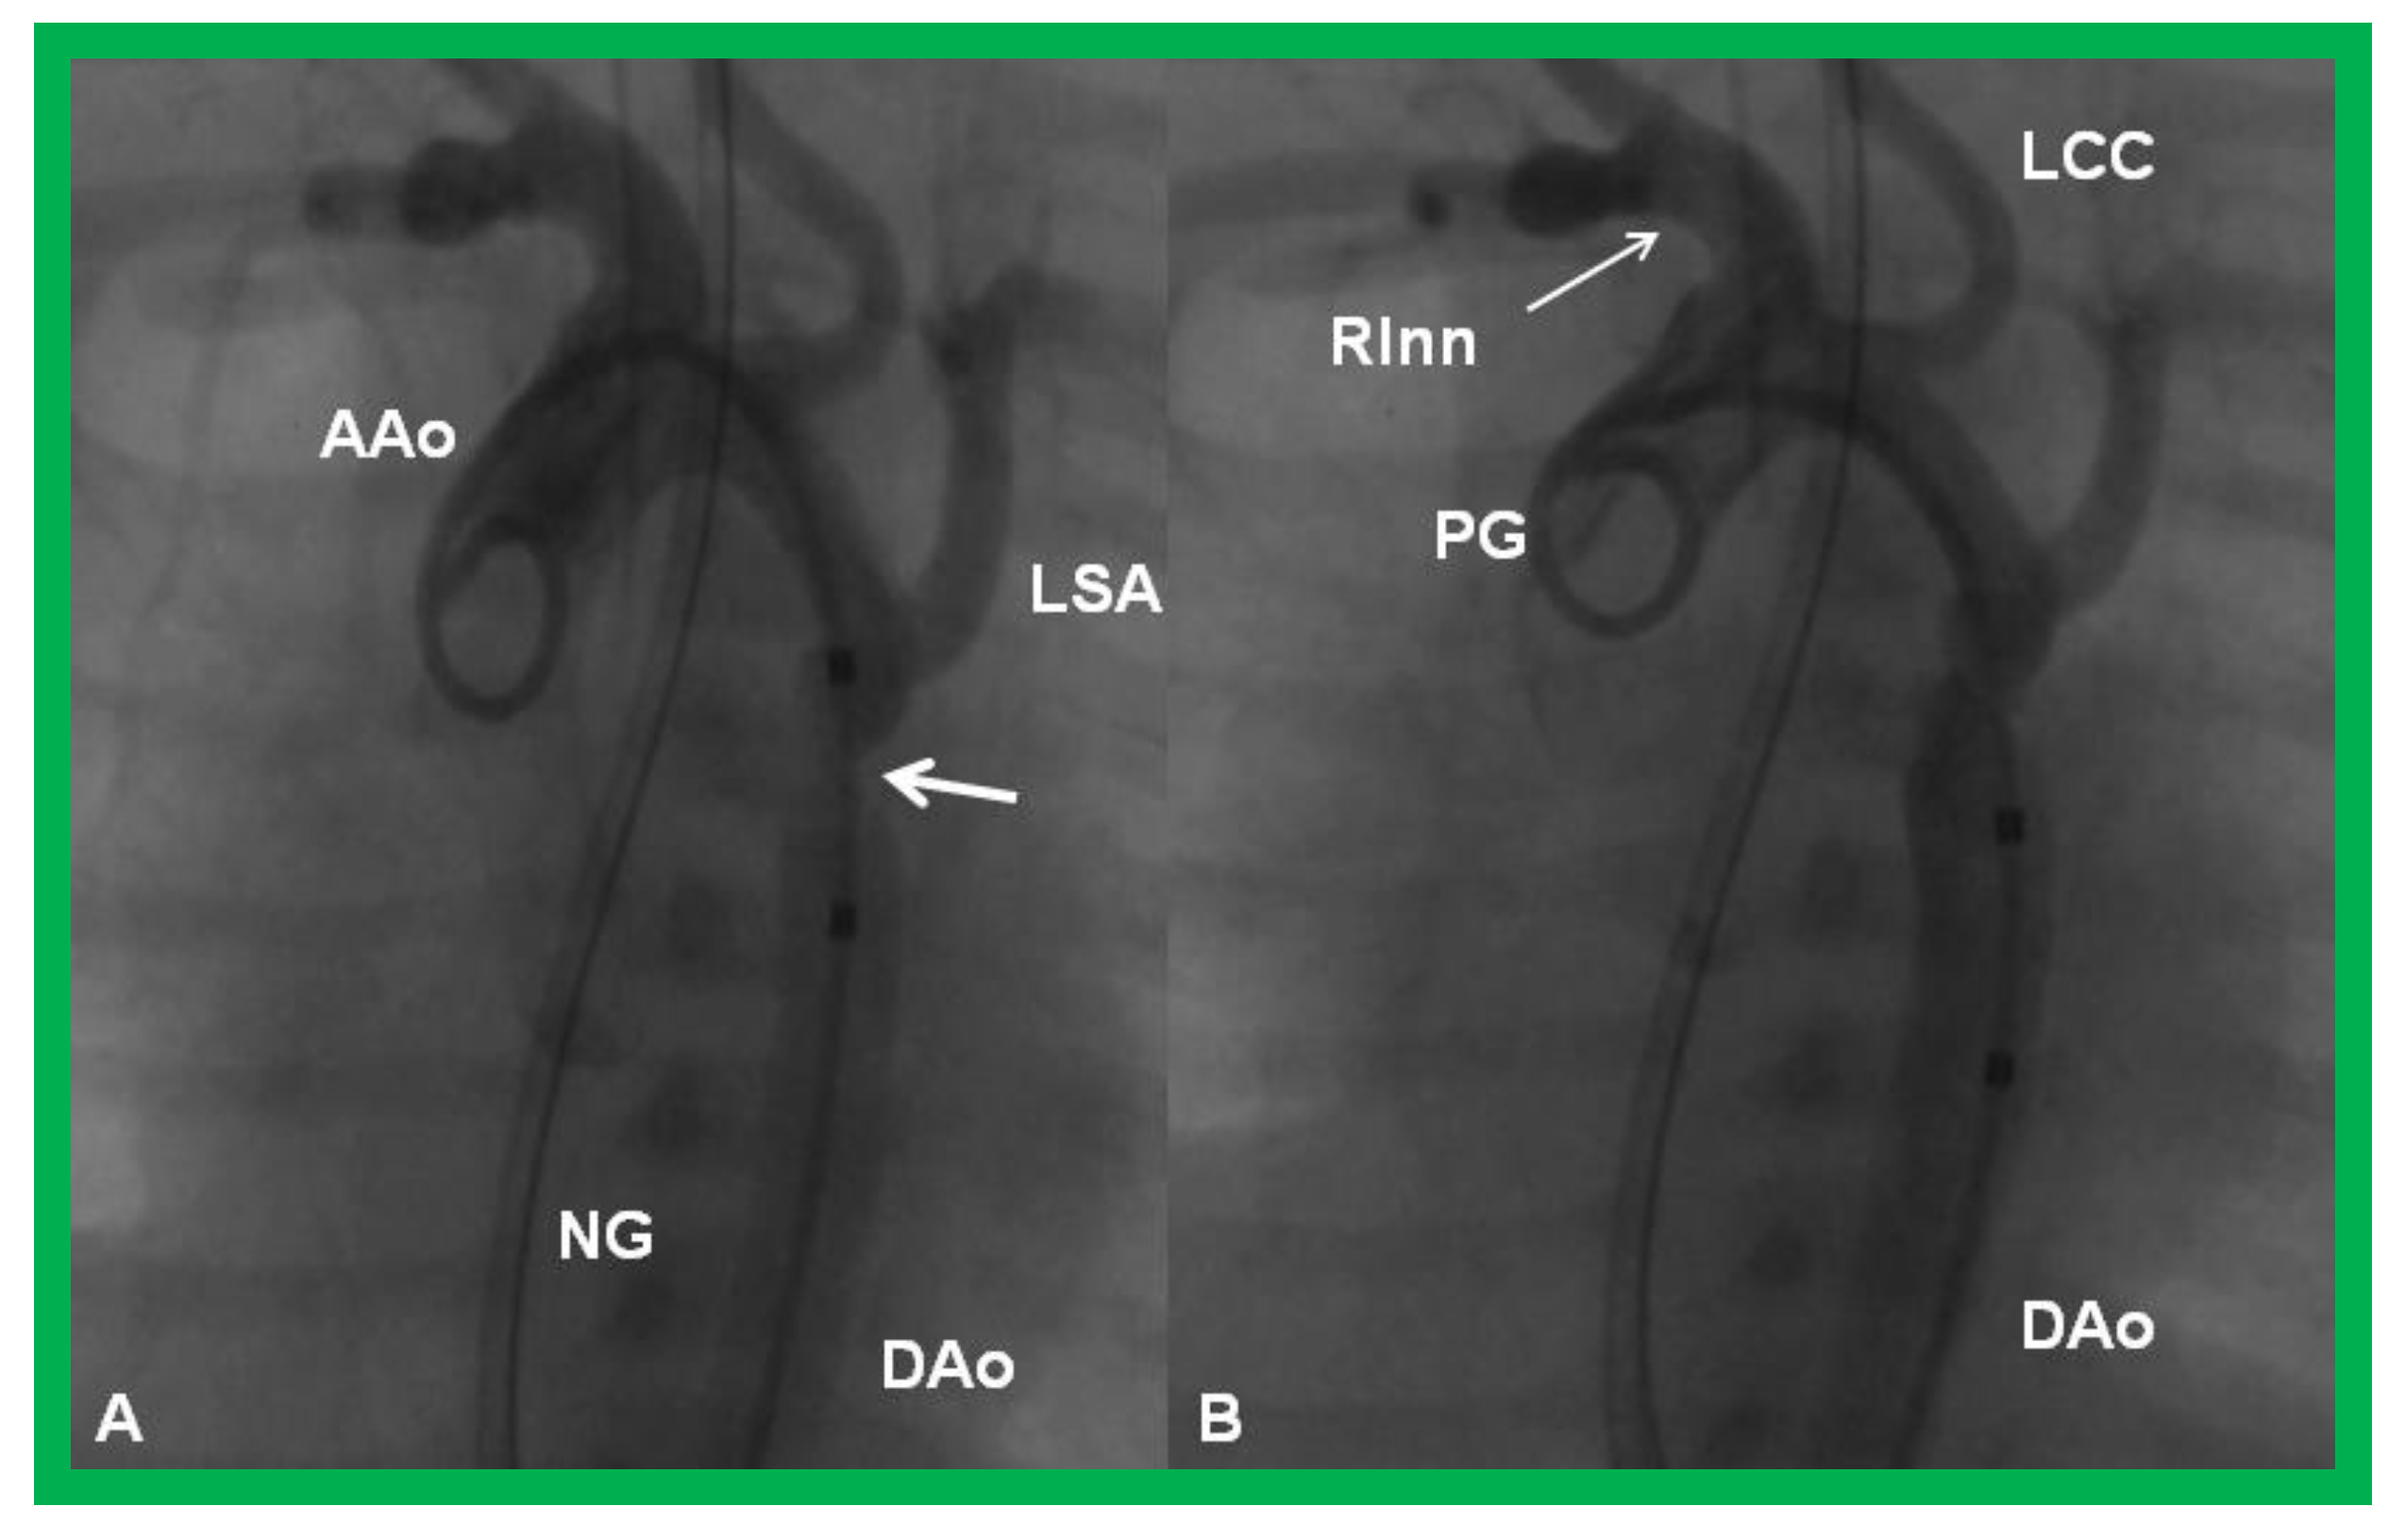

- Rao, P.S.; Balfour, I.C.; Singh, G.K.; Jureidini, S.B.; Chen, S. Bridge stents in the management of obstructive vascular lesions in children. Am. J. Cardiol. 2001, 88, 699–702. [Google Scholar] [CrossRef]

- Rao, P.S. Stents in the management of congenital heart disease in the pediatric and adult patients. Indian Heart J. 2001, 53, 714–730. [Google Scholar] [PubMed]

- Sahu, R.; Rao, P.S. Transcatheter stent therapy in children: An update. Pediatrics Ther. 2012, S5. [Google Scholar] [CrossRef]

- Rao, P.S. Stents in the Management of Vascular Obstructive Lesions Associated with Congenital Heart Disease. In Cardiac Catheterization and Imaging (From Pediatrics to Geriatrics); Vijayalakshmi, I.B., Ed.; Jaypee Publications: New Delhi, India, 2015; pp. 573–598. [Google Scholar]

- Rao, P.S. Stents. In Pediatric Cardiology: How It Has Evolved Over The Last 50 Years; Rao, P.S., Ed.; Cambridge Scholars Publishing: New Castle upon Tyne, UK, 2020; pp. 511–559. ISBN 9781527548886. [Google Scholar]